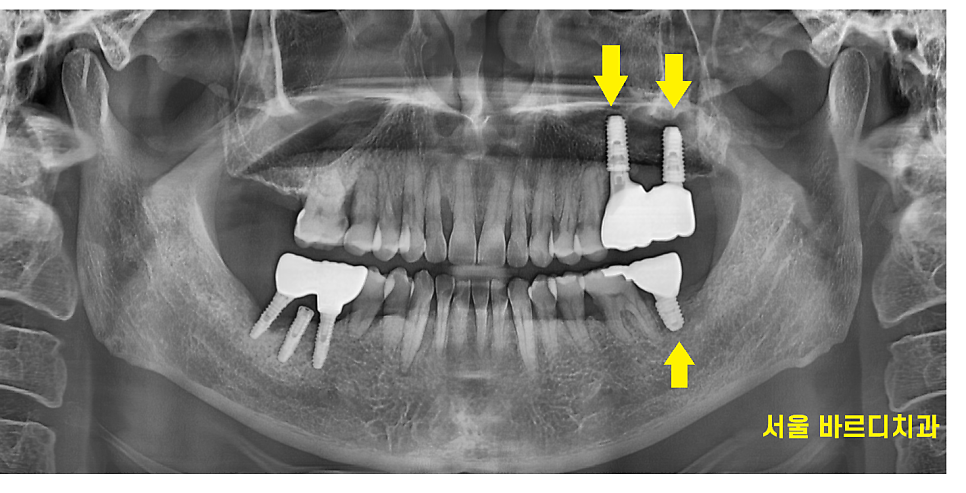

240920

오늘 환자분도 가장 문제가 되는 부분부터

발치 후 임플란트 치료를 하셨답니다.